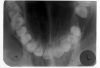

The purpose of the intraoral periapical examination is to obtain a view of the entire tooth and its surrounding structures, as in Figure 1. Two exposure techniques may be employed for periapical radiography: the paralleling technique and the bisecting angle technique. The paralleling technique is the preferred method. This technique provides less image distortion and reduces excess radiation to the patient. The paralleling technique should always be attempted before other techniques. The bisecting technique can be employed for patients unable to accommodate the positioning of the paralleling technique. Candidates may include those with low palatal vaults and children. Disadvantages to the bisecting technique include image distortion and excess radiation due to increased angulations involving the eye and thyroid glands. Regardless of the technique, however, the rules of radiography referred to earlier must be followed.

Figure 1 - Periapical Image

Figure 1